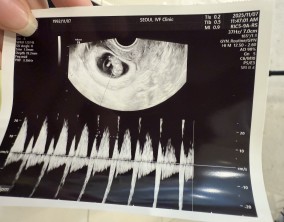

심장소리 이후, 함께 웃게 된 임밍아웃

유정원장님 치료 과정 내내 항상 따뜻하게 진료해 주셔서 감사한 마음이 큽니다. 덕분에 불안한 순간에도 마음을 다잡고 치료를 이어갈 수 있었습니다.